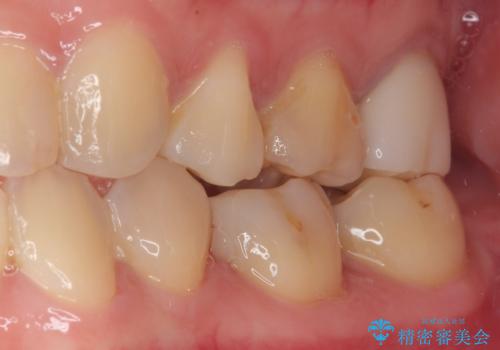

歯と歯茎の間に圧排糸と言われる糸を入れてシリコーン印象材にて型どりをしました。

ハイブリッドインレーの装着時には、唾液の侵入を防ぐために、ラバーダム防湿を行いました。